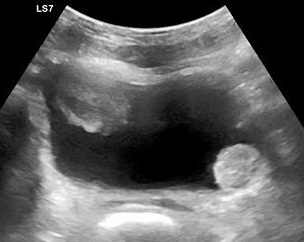

- Figure 2. Moderate hydronephrosis demonstrating location of ureter (surrounded by arrows) exiting renal pelvis

- The primary sonographic abnormality you will identify in the patient with suspected renal colic is hydronephrosis. The degree of hydronephrosis relates to the degree and extent of obstruction: (Illustration 2, Videos 11-17)

- After complete obstruction to flow, there is an acute rise in intrarenal pressure. The renal pelvis and calyces dilate first. On US you will see echo-free areas distending the normal bright (echogenic) central area of the kidney.

- As obstruction continues, the renal parenchyma becomes compressed and you see thinning of the pyramids.

- Videos 14-15. Moderate hydronephrosis